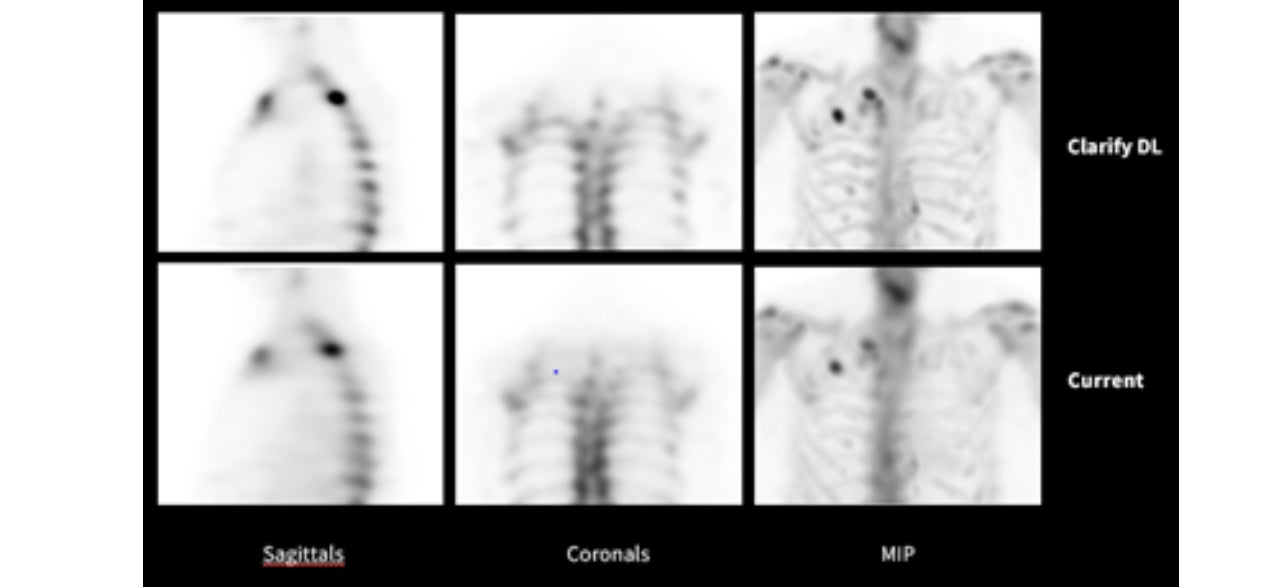

AI*を用いた骨SPECTのノイズ低減技術:Clarify DL

核医学における画像再構成の技術はその歴史とともに進化し、昨今ではBSREM法(画像再構成の演算の中にノイズ抑制のパラメータを加えることでノイズを制御しながら逐次近似再構成を行う技術)などが採用されてきました。今回、GEヘルスケアは新たな技術として骨SPECTにAI*を用いてコントラストと空間分解能を維持しながらノイズを抑制する技術を採用しました。ノイズ低減による更なる高画質化により、臨床的有用性の向上を目指します。

*AIはノイズを抑制するものであり、自己学習するものではありません。